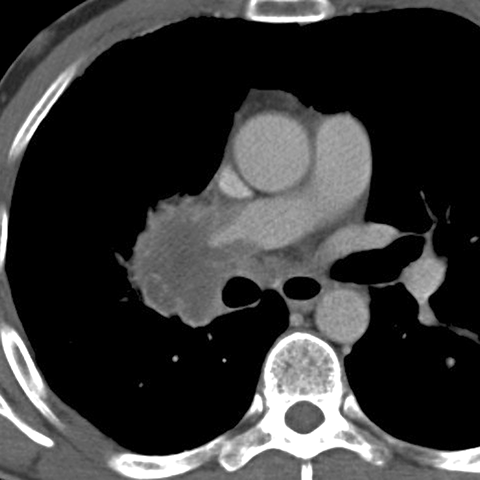

Hilar Nodes in Lung Cancer [2 of 3]